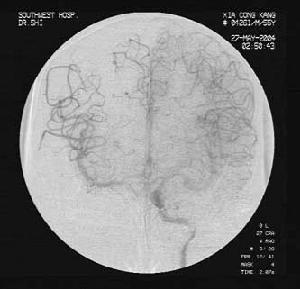

本病的診斷主要依靠病史和臨床表現,腹部x線平片顯示受累小腸、結腸輕度或中度擴張脹氣,晚期由於腸腔和腹腔內大量積液,平片顯示腹部普遍密度增高。選擇性動脈造影對診斷有重要意義,早期可有助於鑑別血管栓塞、血栓形成或痙攣,並可同時給予血管擴張劑等治療。